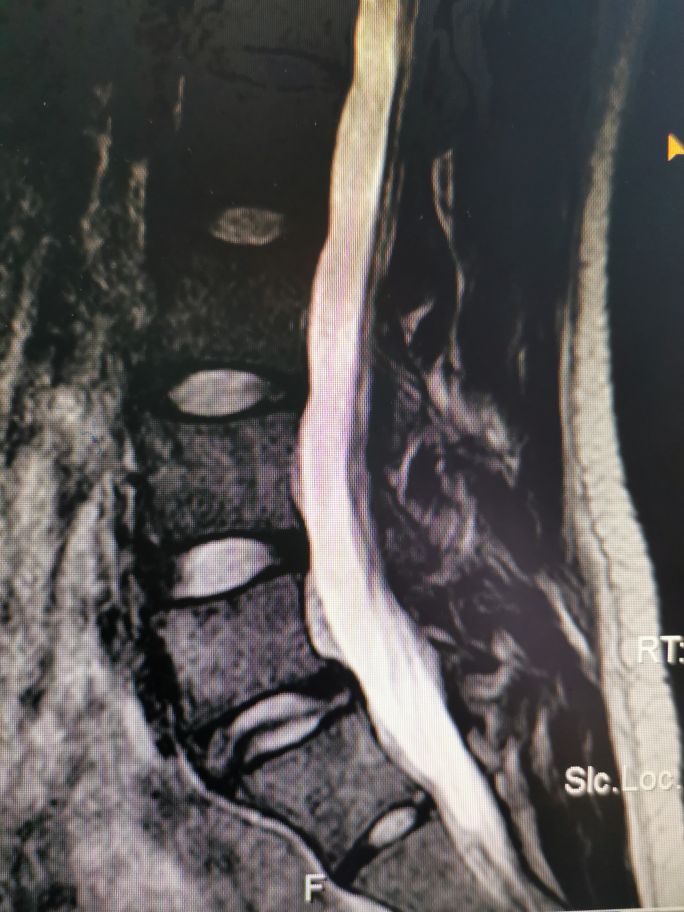

磁共振上看到腰5的后缘相对于骶1的后缘前移了大概1/4椎体(正常应该对齐的),像这种上位椎体相对于下位椎体前移的就叫腰椎滑脱。腰椎滑脱按病因分类,具体可分为椎弓发育不良性、椎弓峡部裂性、退行性、外伤性、病理性和医源性导致的腰椎滑脱等。临床上以椎弓峡部裂性滑脱及退行性滑脱多见。腰椎滑脱的程度分级有多种,常用针对椎弓峡部裂性滑脱的Meyerding分级如下:

这样说比较抽象,其实最简单的办法就是把椎体分为四等份,超出1/4就是I度滑脱,超出2/4就是II度滑脱,依次类推。具体到这个病人,她上位椎体超出下位椎体1/4,那就是I度滑脱。那这个病人为什么会滑脱呢,也就是她属于何种类型的滑脱呢?首先她年纪很轻,不可能是退变性滑脱,大家看她的x线片:

圈子里面标记的部位是椎弓根峡部,大家看她的椎弓根那里已经断了,所以她这个属于椎弓根峡部裂导致的滑脱,也就是真性滑脱(椎弓根未断的滑脱是假性滑脱)。